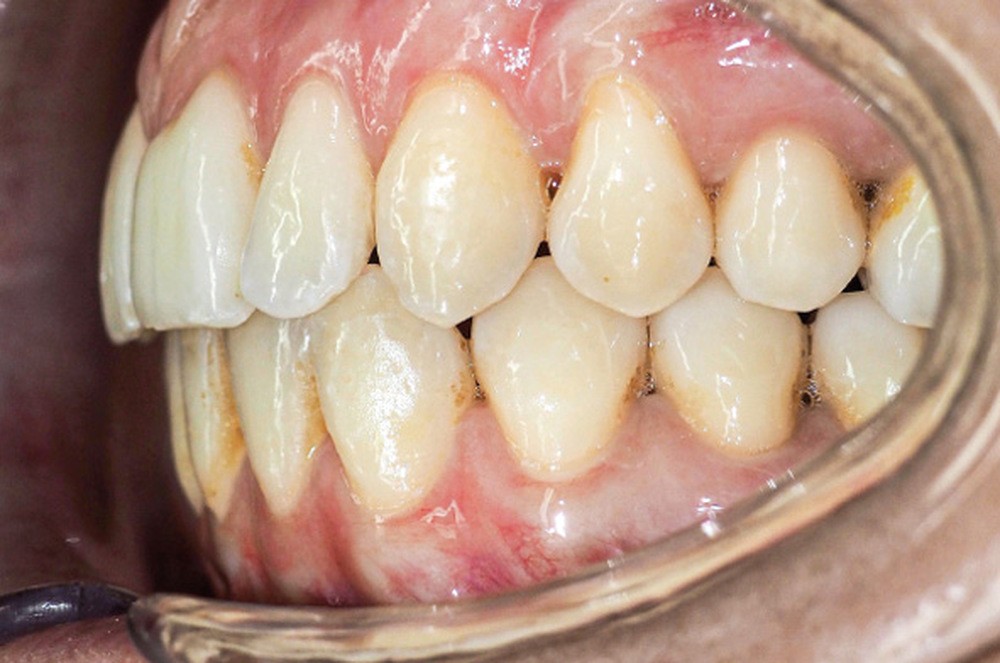

Discussion (fig. 4 à 7)

La durée du traitement a été de vingt-trois mois. Des mouvements lents ont permis un contrôle des axes incisifs mandibulaires.

Des triangles noirs sont apparus à la mandibule suite à l’extraction de 31 : ils ne sont pas exposés lors du sourire, ce qui n’entraîne pas de défaut esthétique.

La génioplastie discrète apporte un équilibre facial et une fermeture labiale non forcée, ce qui limite le risque de récidive liée à la pression musculaire.

La superposition des structures anatomiques nous montre une ingression de l’incisive mandibulaire et un maintien de l’axe ainsi qu’une distalisation en gression de l’incisive maxillaire.